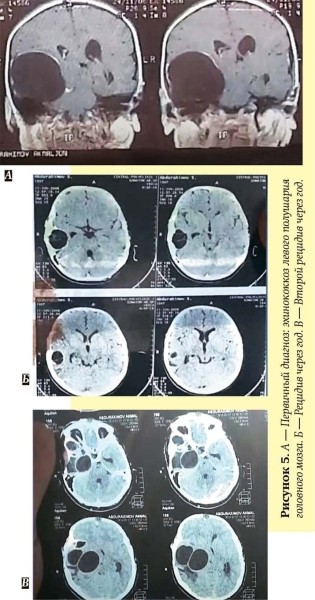

Рецидивирующий эхинококкоз головного мозга. Пациент 1998 г. р., г. Термез (Узбекистан). Первичный диагноз: эхинококкоз левого полушария головного мозга. Назначен албендазол по 400 мг 2 раза в сутки в течение 28 дней. Через год — рецидив эхинококкоза в левом полушарии. Выполнена повторная операция. Вновь назначен албендазол по 400 мг дважды в сутки на 3 месяца, затем чередование приема препарата в течение 4 дней с 3 днями перерыва в течение 6 месяцев. Через год — еще один рецидив: в том же операционном поле сформировалась новая киста: пациент прооперирован в третий раз (см. рис. 5) После консилиума назначен албендазол ежедневно по 800 мг в день в 2 приема без перерывов в лечении на протяжении не менее 5 лет. В настоящее время терапия продолжается. Рецидива нет.

По мнению Сергея Козлова, причиной рецидивов эхинококкоза у данного пациента стали грубые ошибки в послеоперационной противопаразитарной терапии: короткий курс после первой операции, перерывы в терапии после операции по поводу рецидива.